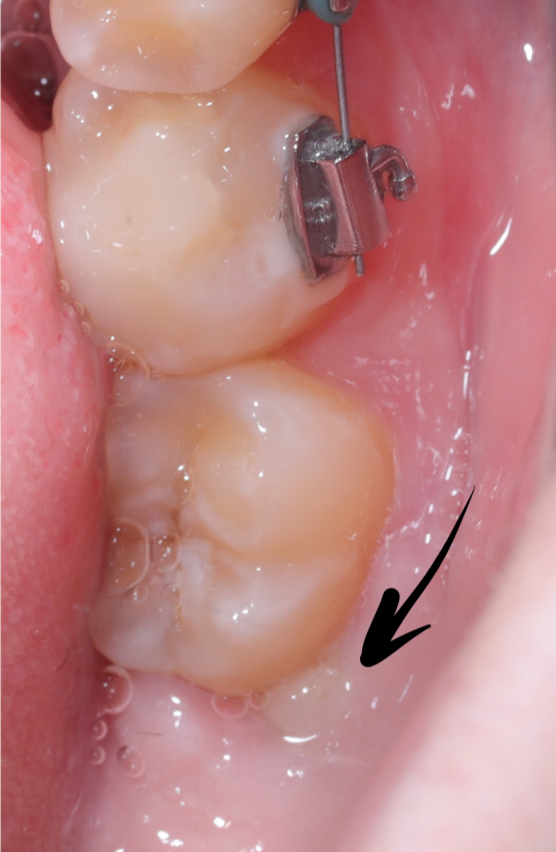

Удаление зубов мудрости, как часть программы ортодонтического лечения!

Вот 4 маленьких операции, которые мы провели в течение месяца в рамках подготовки пациента к установке брекетов.

Я очень много работаю с ортодонтами: иногда они помогают мне создать необходимое пространство для установки импланта и дальнейшего протезирования, а иногда я удаляю «злые» зубы мудрости, чтобы облегчить им течение процесса лечения.